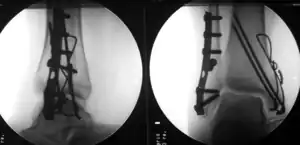

| Surgically treated bimalleolar fracture | |

Surgical treatment will often be required, usually an Open Reduction Internal Fixation. This involves the surgical reduction, or realignment, of the fracture followed by the implementation of surgical implants to aid in the healing of the fracture.[2]